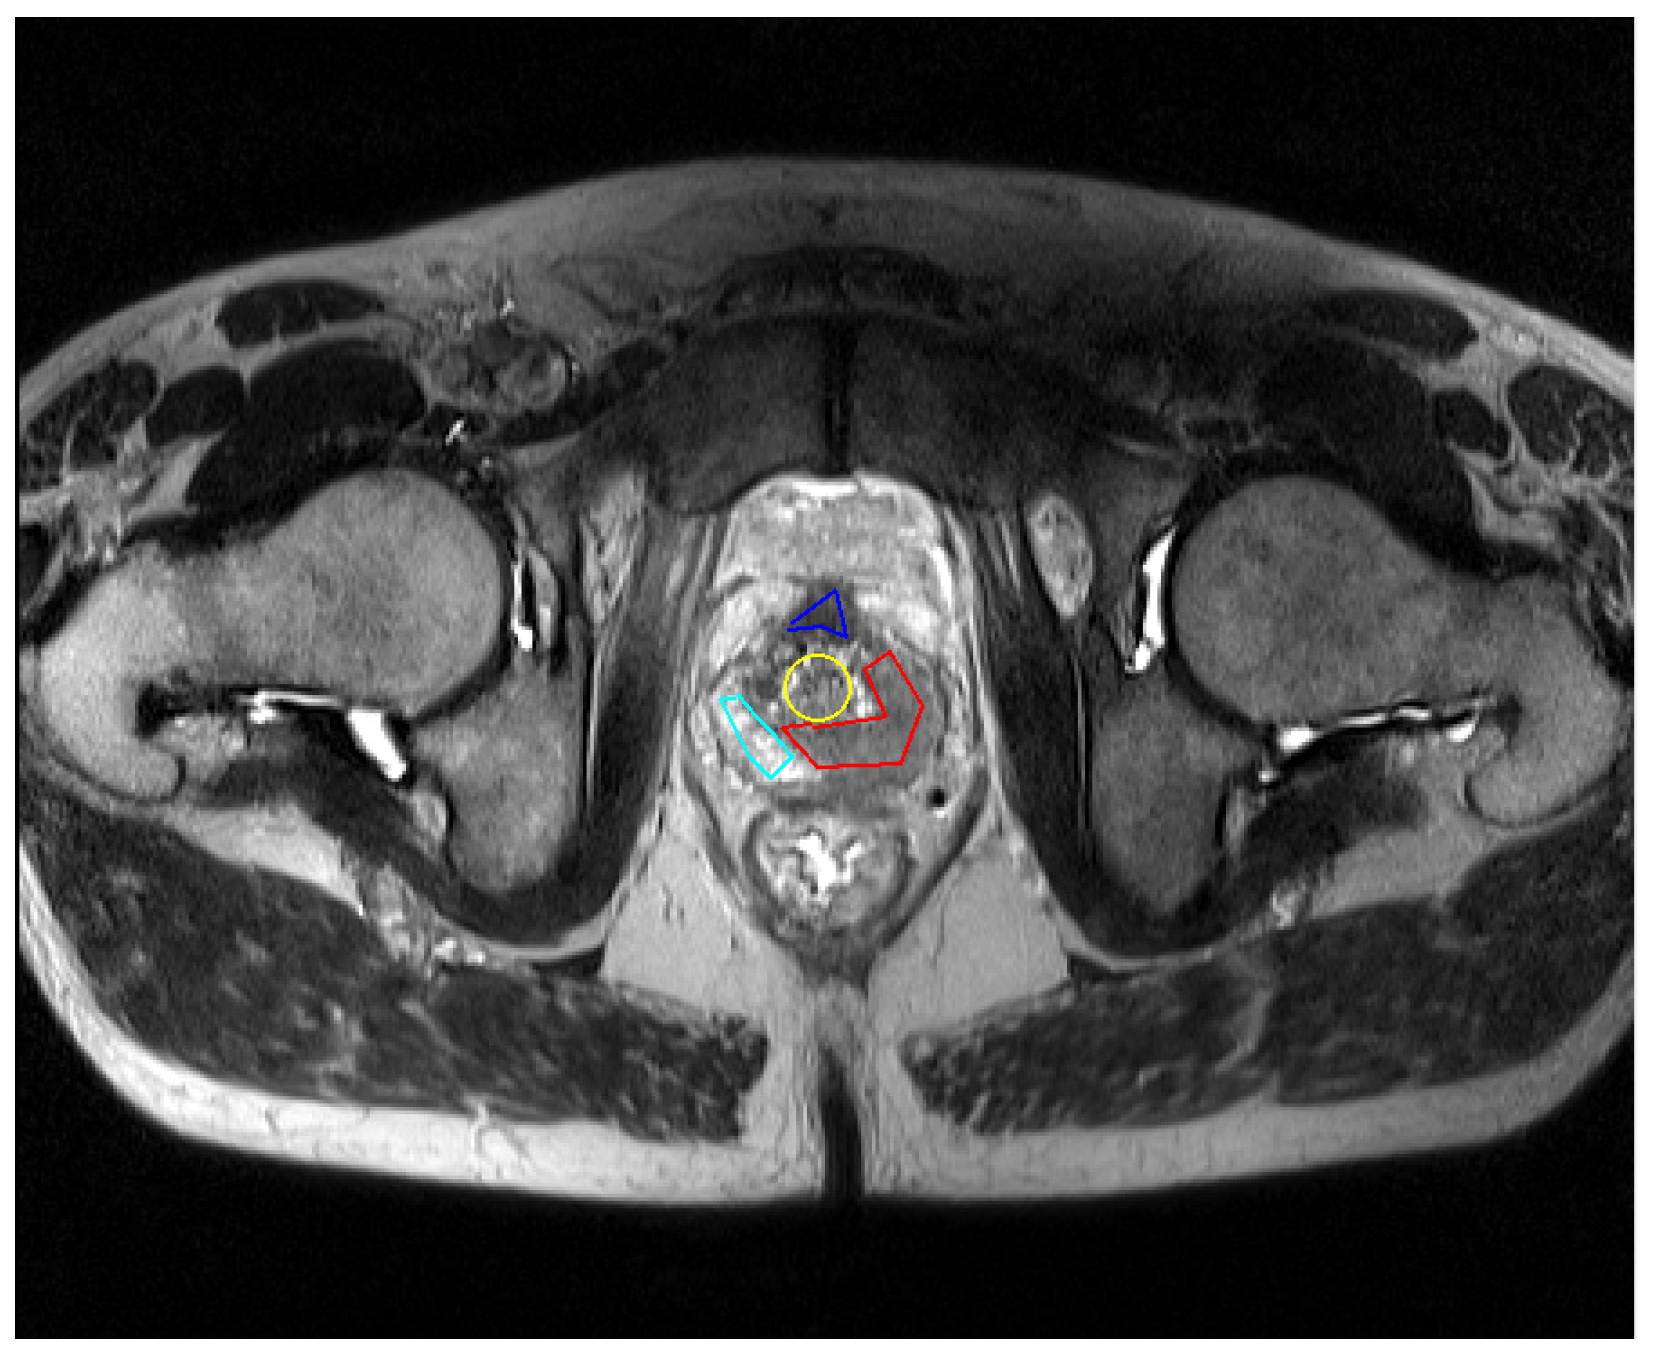

In this section, we present a deep analysis of the results of a single segmentation experiment performed using the implemented algorithms, namely the Basic ACS, Simplified ACS and GVF ACS versions of the snake-based models. For all the cases, the initial contours used for all the zones are shown in Figure 11.

Figure 11. Initialization used for the testing of all the algorithms.